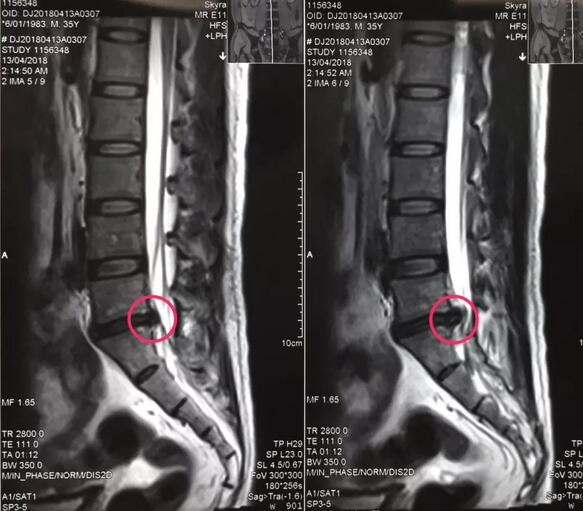

八零后李先生来自山西长治,是家里的顶梁柱,半年前开始出现腰痛不适,工作繁忙没有时间看病,后来突然加重并出现左下肢放射样抽痛,走路都走不了,在当地多家医院检查确诊为腰椎间盘突出症,治疗方案都是开刀手术,打钉固定,小李拒绝开放手术,回家卧床四个多月,仍然不能下地走路,亲朋友好友四处寻医问药,终于从病友群里打听到,色花堂 可以微创手术,效果很好,就专程前来。骨一科专家团队给李先生进行了详细的查体和认真的读片,告诉李先生诊断确实是腰椎间盘突出症,适合孔镜微创,不用开放手术,不用打钉固定,李先生欣然接受。7月27日,骨一科微创团队为李先生实施了经皮椎间孔镜下髓核摘除术,手术一小时,术后下肢抽痛症状完全解除,终于可以下地走路了,李先生和家人对手术效果非常满意。